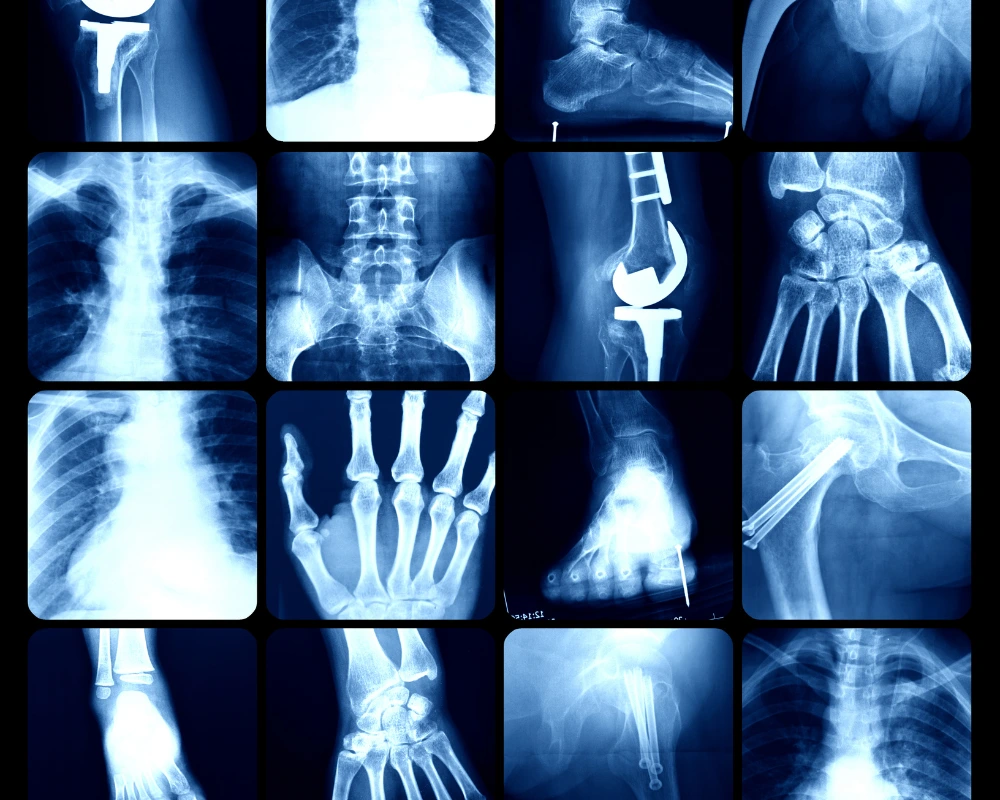

Maximum Resolution Imaging is one of the top diagnostic imaging centers in Texas, specialized in advanced MRI, and CT scanning. Our imaging machines for CT Scan, MRI and X Ray are some of the world’s most sophisticated, high-tech equipment. Our state-of-the-art imaging facility provides rapid, high-quality results with immediate and accurate diagnostics.

Medical Imaging Services We Offer

We proudly provide a wide range of imaging services catering to both corporate entities and individual clients. Our superior imaging capabilities position us as the preferred choice for healthcare providers across Texas seeking precise diagnostic imaging solutions for their patients.

From Advanced diagnostic imaging to specialized procedures, our commitment to excellence ensures that you receive the highest quality care. Explore our most in-demand services below and discover how we can assist you on your journey to optimal health and wellness.